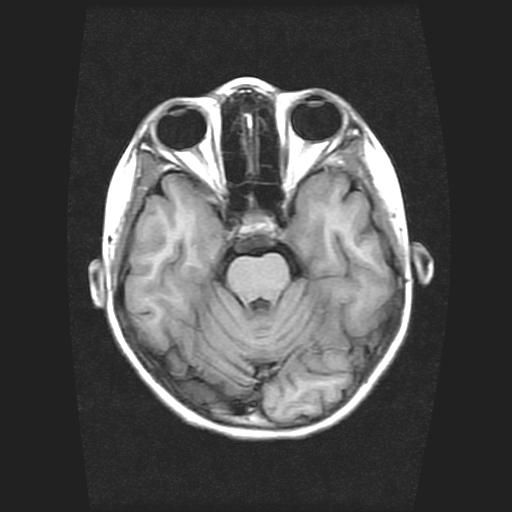

标题: PED0378:女孩9岁,癫痫,看能否停药 [打印本页]

标题: PED0378:女孩9岁,癫痫,看能否停药

9岁女孩,三岁时诊断为癫痫,一直服丙戊酸钠,现患者一般情况良好,家长复查核磁片,看能否停药..

巨脑回